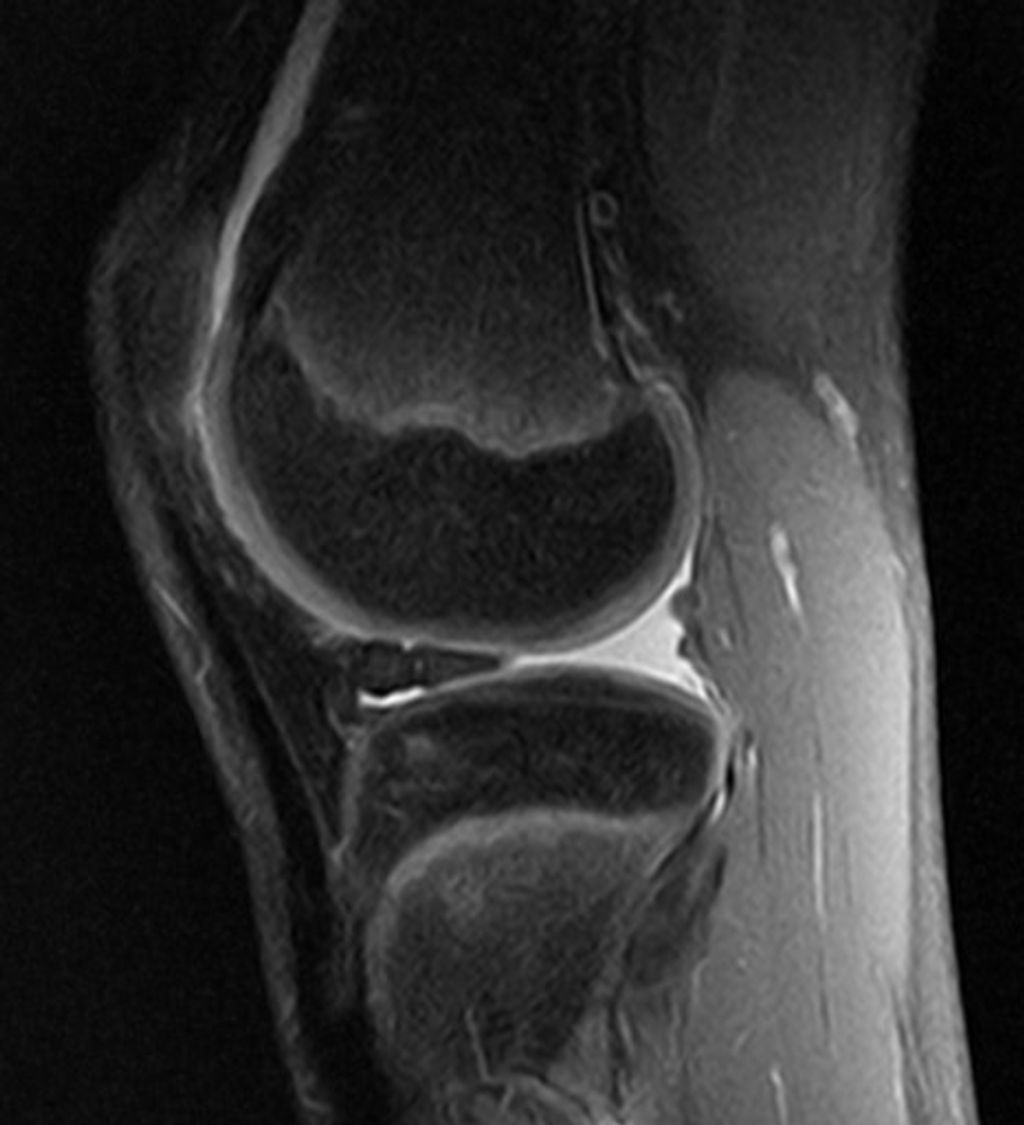

After recognizing the symptoms of osteoarthritis knee pain, we proceed to its diagnosis, which is crucial for tailoring the most effective management strategies. We begin with a thorough medical history and a physical examination. The presence of joint stiffness, swelling, and pain during movement can be indicative of osteoarthritis. To confirm the diagnosis, imaging tests such as X-rays or MRI scans are often employed. These tests reveal the extent of joint damage, including loss of cartilage and changes in bone structure.

Imaging Tests for Osteoarthritis Knee Pain:

• X-rays: Show bone spurs and cartilage loss

• MRI: Provides detailed images of soft tissues

To further assess the condition, we may also employ magnetic resonance imaging (MRI) to visualize soft tissue structures, including cartilage, ligaments, and the meniscus. However, an MRI is not always necessary for diagnosis, as the clinical presentation and X-rays often suffice.